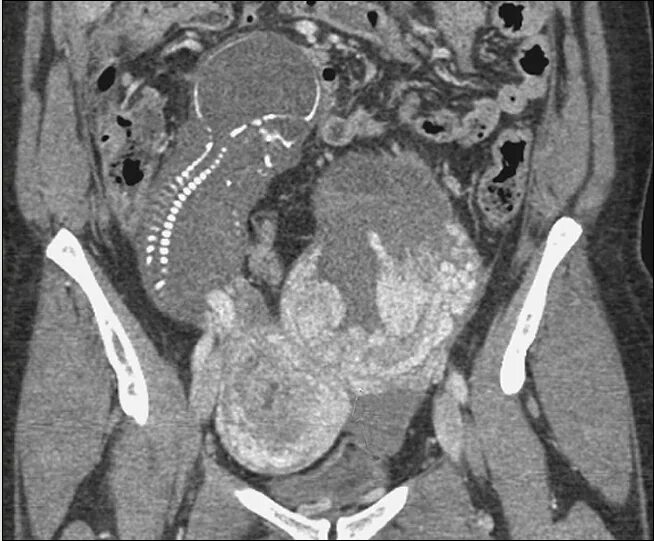

Яйцеклетка в брюшную полость